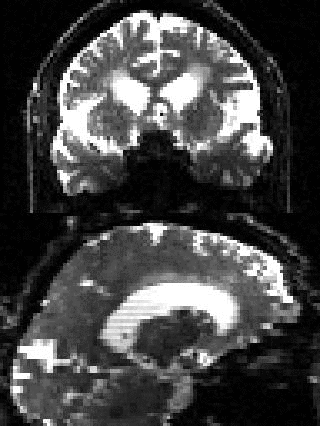

| Example of data with and without outlier-replacement. |

![]() |

| Movie of two adjacent slices alternating between with and without outlier-replacement when running eddy. The images are in "corrected space", *i.e.* after having been registered into the space of the first $b=0$ volume. Note how subject movement has meant that the original drop-out slices have been rotated out-of-plane such that they now appear as dark diagonal bands. |